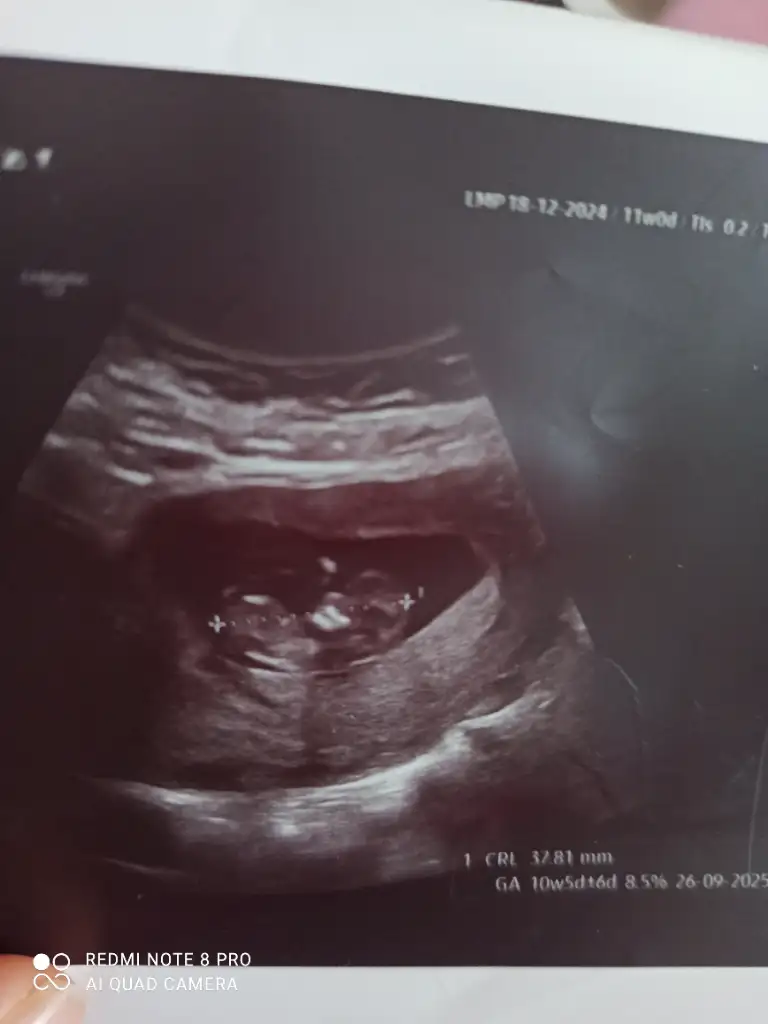

Günaydınlar bugun kontrole gittim 11 Haftalık tam. miniğim büyüyor artık bu heyecanımı sizinle paylaşmak istedim haftaya ikili tarama var cinsiyet için çook erken ama resme bakıp yorum yapabilecek var mı🙂

Eklentiler

• IMG_20250305_105324.webp

IMG_20250305_105324.webp

16 KB · Görüntüleme: 62